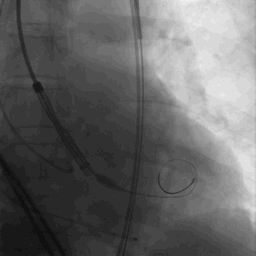

瓣膜释放后

瓣膜释放后形态位置良好,造影无返流。

术后即刻评估

瓣膜释放后主动脉根部造影